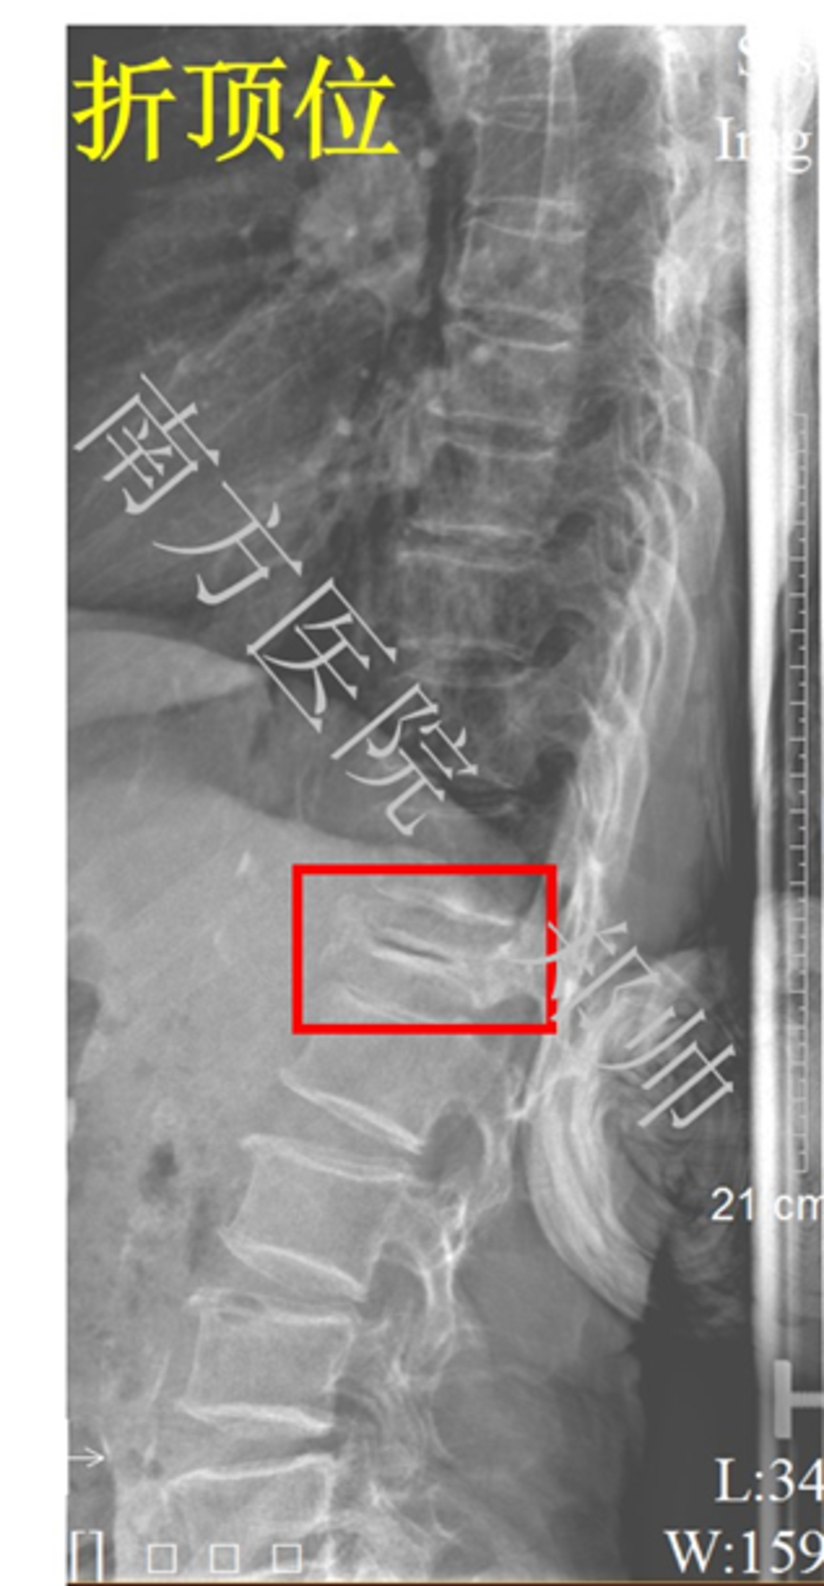

一种新型胸腰椎骨折经皮椎弓根螺钉复位内固定体外撑开器的设计与临床应用研究 中国修复重建外科杂志 唯一官网

什么是kummell病 陈旧性椎体骨折骨 附图 健康号 微医